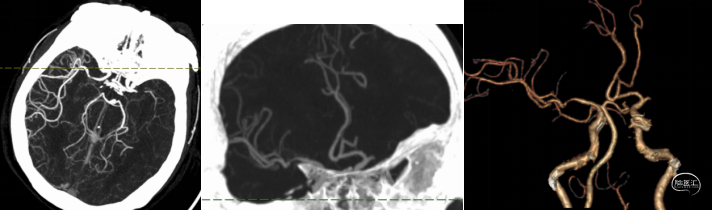

头颅CTA(12/3):左侧大脑中动脉闭塞。

术前造影提示:左侧大脑中动脉闭塞,可见部分豆纹动脉显影,左侧大脑前动脉通过脑膜支代偿左侧大脑中上干。

0.014" 微导丝引导下支架微导管进入M2下干,保留导丝退回微导管,造影提示M2未见显影,考虑“首过效应”阴性。此时考虑病变性质狭窄基础上并大负荷血栓可能,不排除栓塞性病变可能。

微导管到位左侧大脑中动脉下干,造影证实真腔。

沿微导管送入4.0*30mm Syphonet®取栓支架,造影显示:造影见左侧大脑中动脉M1段约1.8cm细长狭窄显影。大脑中动脉一干仍不显影,考虑狭窄明显并血栓形成。以静脉替罗非班推注12ml,同时静脉7ml/h维持。